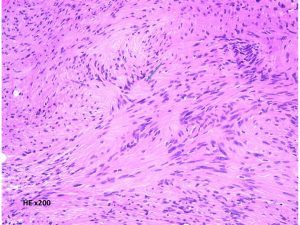

細胞核が円状に並んだ形態で、いわゆるVerocay bodyと呼ばれる所見(矢印)。 HE x200.

紡錐型の核を有する腫瘍細胞で構成されます。左側の写真のように,古典的病理所見として,束状 fascicular に配列する密な組織である Antoni A Typeと網状 reticular で疎な組織である Antoni B Typeが混在するパターンを示します。神経鞘腫では多少の核の異型性がみられても悪性像とはいえません。嚢胞を形成したり,時には毛細血管拡張 simple hemangioma を思わせるような著明な血管の増生があり腫瘍内出血をきたすことがあります。